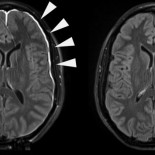

Así se recupera tu cerebro tras un golpe en la cabeza

Después de una lesión en la cabeza, la membrana protectora del cerebro se puede reparar con sorprendente rapidez gracias a la ayuda de un organizadísimo ejército de células inmunitarias. En un nuevo estudio, un equipo de los NHI observaron en tiempo real cómo estas células asumían trabajos para reparar el revestimiento dañado del cerebro, también conocido como las meninges. Estos resultados pueden ayudar a proporcionar pistas sobre el proceso de cura de lesiones leves consecuencia de un golpe leve. Pero no tanto con un segundo traumatismo.